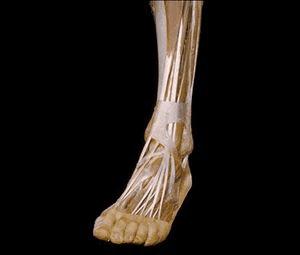

10.对腿和足部进行的解剖显示,长腱把脚趾和足端的血管以及神经连接在一起。